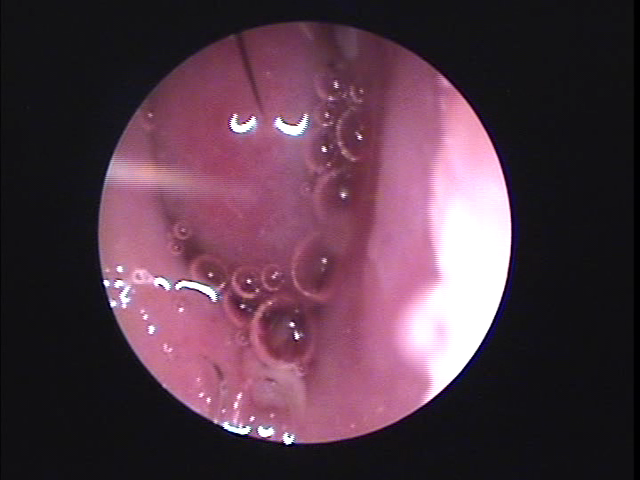

코막힘의 원인으로는 알레르기성 비염, 코 내부의 변형, 감기, 건조한 공기 등이 있습니다. 알레르기성 비염은 미세먼지, 연기, 꽃가루 등이 알레르기를 유발하여 비강의 염증을 악화시키게 됩니다. 또한, 코 내부의 변형은 부비동염(축농증), 비중격만곡증, 하비갑개비후 등이 있으며, 이는 약물로는 근본적인 치료가 어려워 수술을 받아야 하는 경우가 대부분입니다. 그 외에 건조한 공기나 감기 등도 코막힘의 주요 원인이 됩니다.

코막힘이 장기간 지속되거나 심각한 경우에는 전문의의 상담이 필요합니다. 만성 비염, 부비동염 등은 약물 치료나 수술적 치료가 필요할 수 있으므로, 조기 상담을 통해 코막힘 원인을 정확히 파악하고 치료받는 것이 중요합니다. 이 포스팅이 코막힘으로 고생하시는 분들에게 도움이 되었기를 바랍니다.